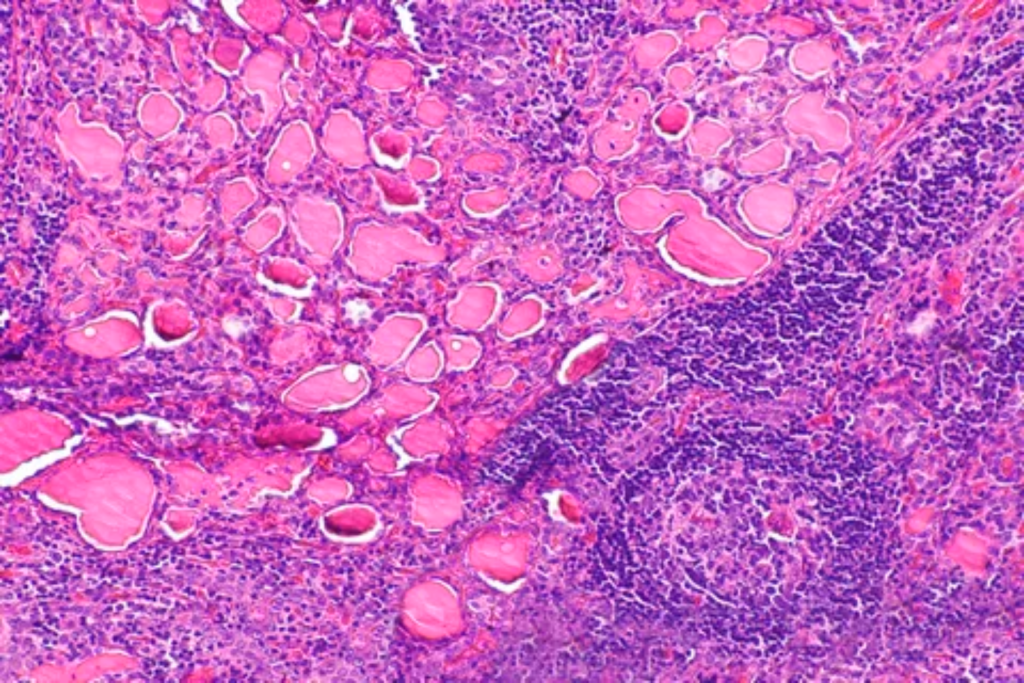

Hashimoto Thyroiditis

Hyperthyroidism

Grave’s disease